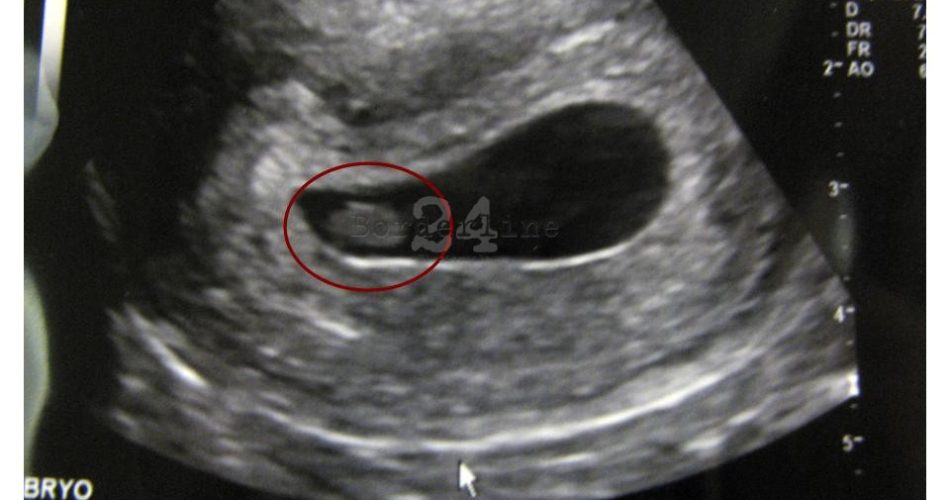

ecografia

Per 13 anni ha portato in grembo il feto gemello del suo ultimo figlio, è accaduto ad una donna di 51 anni di Francavilla Fontana. Dopo 13 anni dall’ultima gravidanza, il 14 febbraio scorso i medici di un ospedale del Veneto le hanno salvato la vita dopo un’emorragia. La notizia è stata pubblicata dal sito brindisino Lo Strillone.

Tutto inizia nel 2005 quando la donna allora 37enne dà alla luce con un cesareo il suo quarto figlio. Un maschietto in buona salute. Sembrava essere andato tutto bene, anche se lei continuava ad avere degli strani dolori. Per 13 anni ha preso antidolorifici, un anno e mezzo fa poi ha iniziato ad avere delle perdite. Il 7 gennaio scorso la situazione precipita, i dolori diventano insopportabili.

La donna viene portata d’urgenza in ospedale dove le vengono fatte cinque trasfusioni di sangue. Alla fine qualcuno capisce cosa sta realmente accadendo e viene sottoposta ad un cesareo: all’interno c’era piccolo feto finito in un’altra placenta rispetto al suo gemello nato 13 anni prima. Il feto si era spostato a destra dell’addome e in tutti questi anni le ecografie non erano riuscite a rilevarlo.